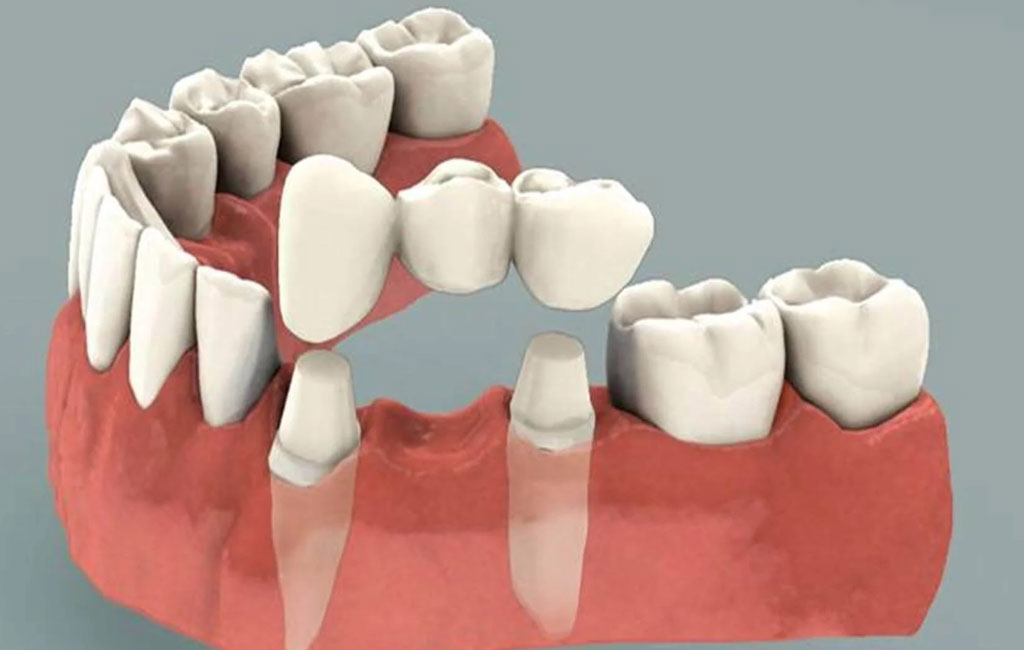

هزینه ی پروتز دندان به عواملی مانند وضعیت دهان و دندان بیمار، نوع پروتز دندان، جنس مواد به کار رفته برای ساخت پروتز، هزینه مرکز دندانپزشکی و تخصص دندانپزشک بستگی دارد. پروتز دندان ناکامل یا پارشیل برای افرادی مناسب است که تنها تعدادی از دندانهایشان را از دست داده اند. اما پروتز کامل برای افرادی مناسب می باشد که دندان های خود را به صورت کامل از دست داده اند. انواع پروتز ثابت شامل روکش دندان، بریج دندان، پروتز ثابت بر پایه ایمپلنت می باشد. گاهی اوقات امکان استفاده از پروتز ثابت وجود ندارد. در این مواقع، دندانپزشک استفاده از پروتزهای متحرک را پیشنهاد می کند. پروتز متحرک را می توانید هر موقع خواستید داخل دهان بگذارید و بردارید. بنابراین، پروتز متحرک می تواند برای عده ای از افراد بهتر از پروتز ثابت باشد.